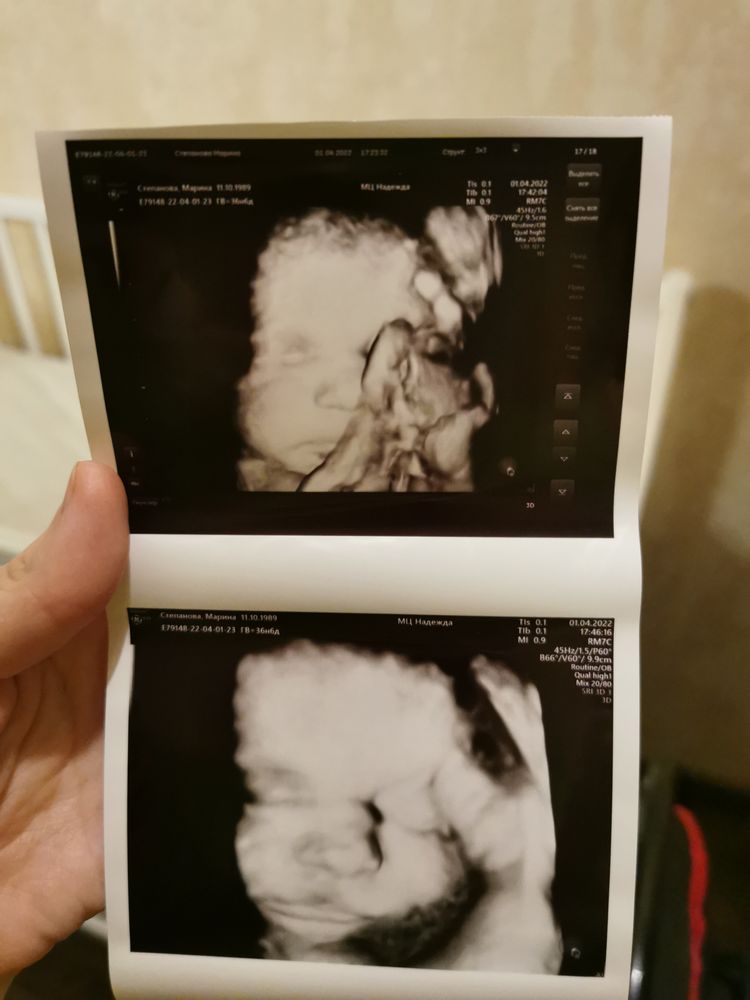

Кто делал 4Д узи при беременности, детки получились похожие на фото? Нам вот сделали фотокарточку на узи, на фото эта креветка вообще ни на кого из семьи не похожа 😂 Муж говорит «Это не мой ребёнок, неси обратно». (В шутку конечно) Носик я так понимаю приплюснутый у деток, пока они в пузыре находятся.

Мне кажется похожа))

Мне вообще кажется , что дети все в этом возрасте и на 4д узи тем более, одинаковые. Позавчера свою смотрели на 4 д и от вашей бы её не отличила 😅

Akhmadalieva, тоже самое хотела сказать....все похожи между собой, глазки закрыты, носики отекшие